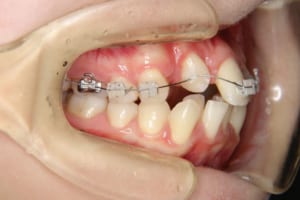

治療中

使用した装置 マルチブラケット装置(唇側矯正)

InVuブラケット

シルバーワイヤー

ホールディングアーチ

歯科矯正用アンカースクリュー(1本)